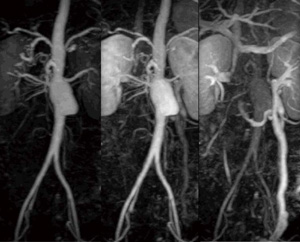

また,造影タイミングをあまり考える必要のないTRICKS-XVの特徴を生かして,造影剤の投与を3回に分けてTRICKS-XVを3回適用し,最も必要とするフェイズのデータをMIP処理することで,広範囲の造影MRAを確実かつ高画質で提供することも可能である(図7)。

図7 3回のTRICKS-XV撮像による腹部〜下肢動脈撮像(画像ご提供:市立旭川病院様)

図7 3回のTRICKS-XV撮像による腹部〜下肢動脈撮像

(画像ご提供:市立旭川病院様)